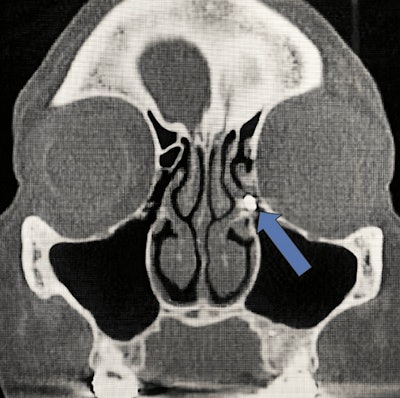

A comprehensive otorhinolaryngological exam revealed hypertrophic turbinates and a mild septal deviation, and a computed tomography (CT) scan of the paranasal sinuses confirmed a 3-mm radiopaque FB near the left maxillary infundibulum, with minimal left ethmoid sinus mucosal thickening. Despite the findings, she chose nonoperative management of the problem, the authors wrote.

Metal foreign body in the ethmoid infundibulum. Image courtesy of Kramer et al. Licensed under CC BY 4.0.

Another CT scan of the sinuses appeared to show what was most likely amalgam that moved from her maxilla to the ethmoid infundibulum, where it became stuck between the uncinate process and ethmoid bulla. Furthermore, the foreign body seemed to have eroded into the bulla and ethmoid air cell mucosal thickening.